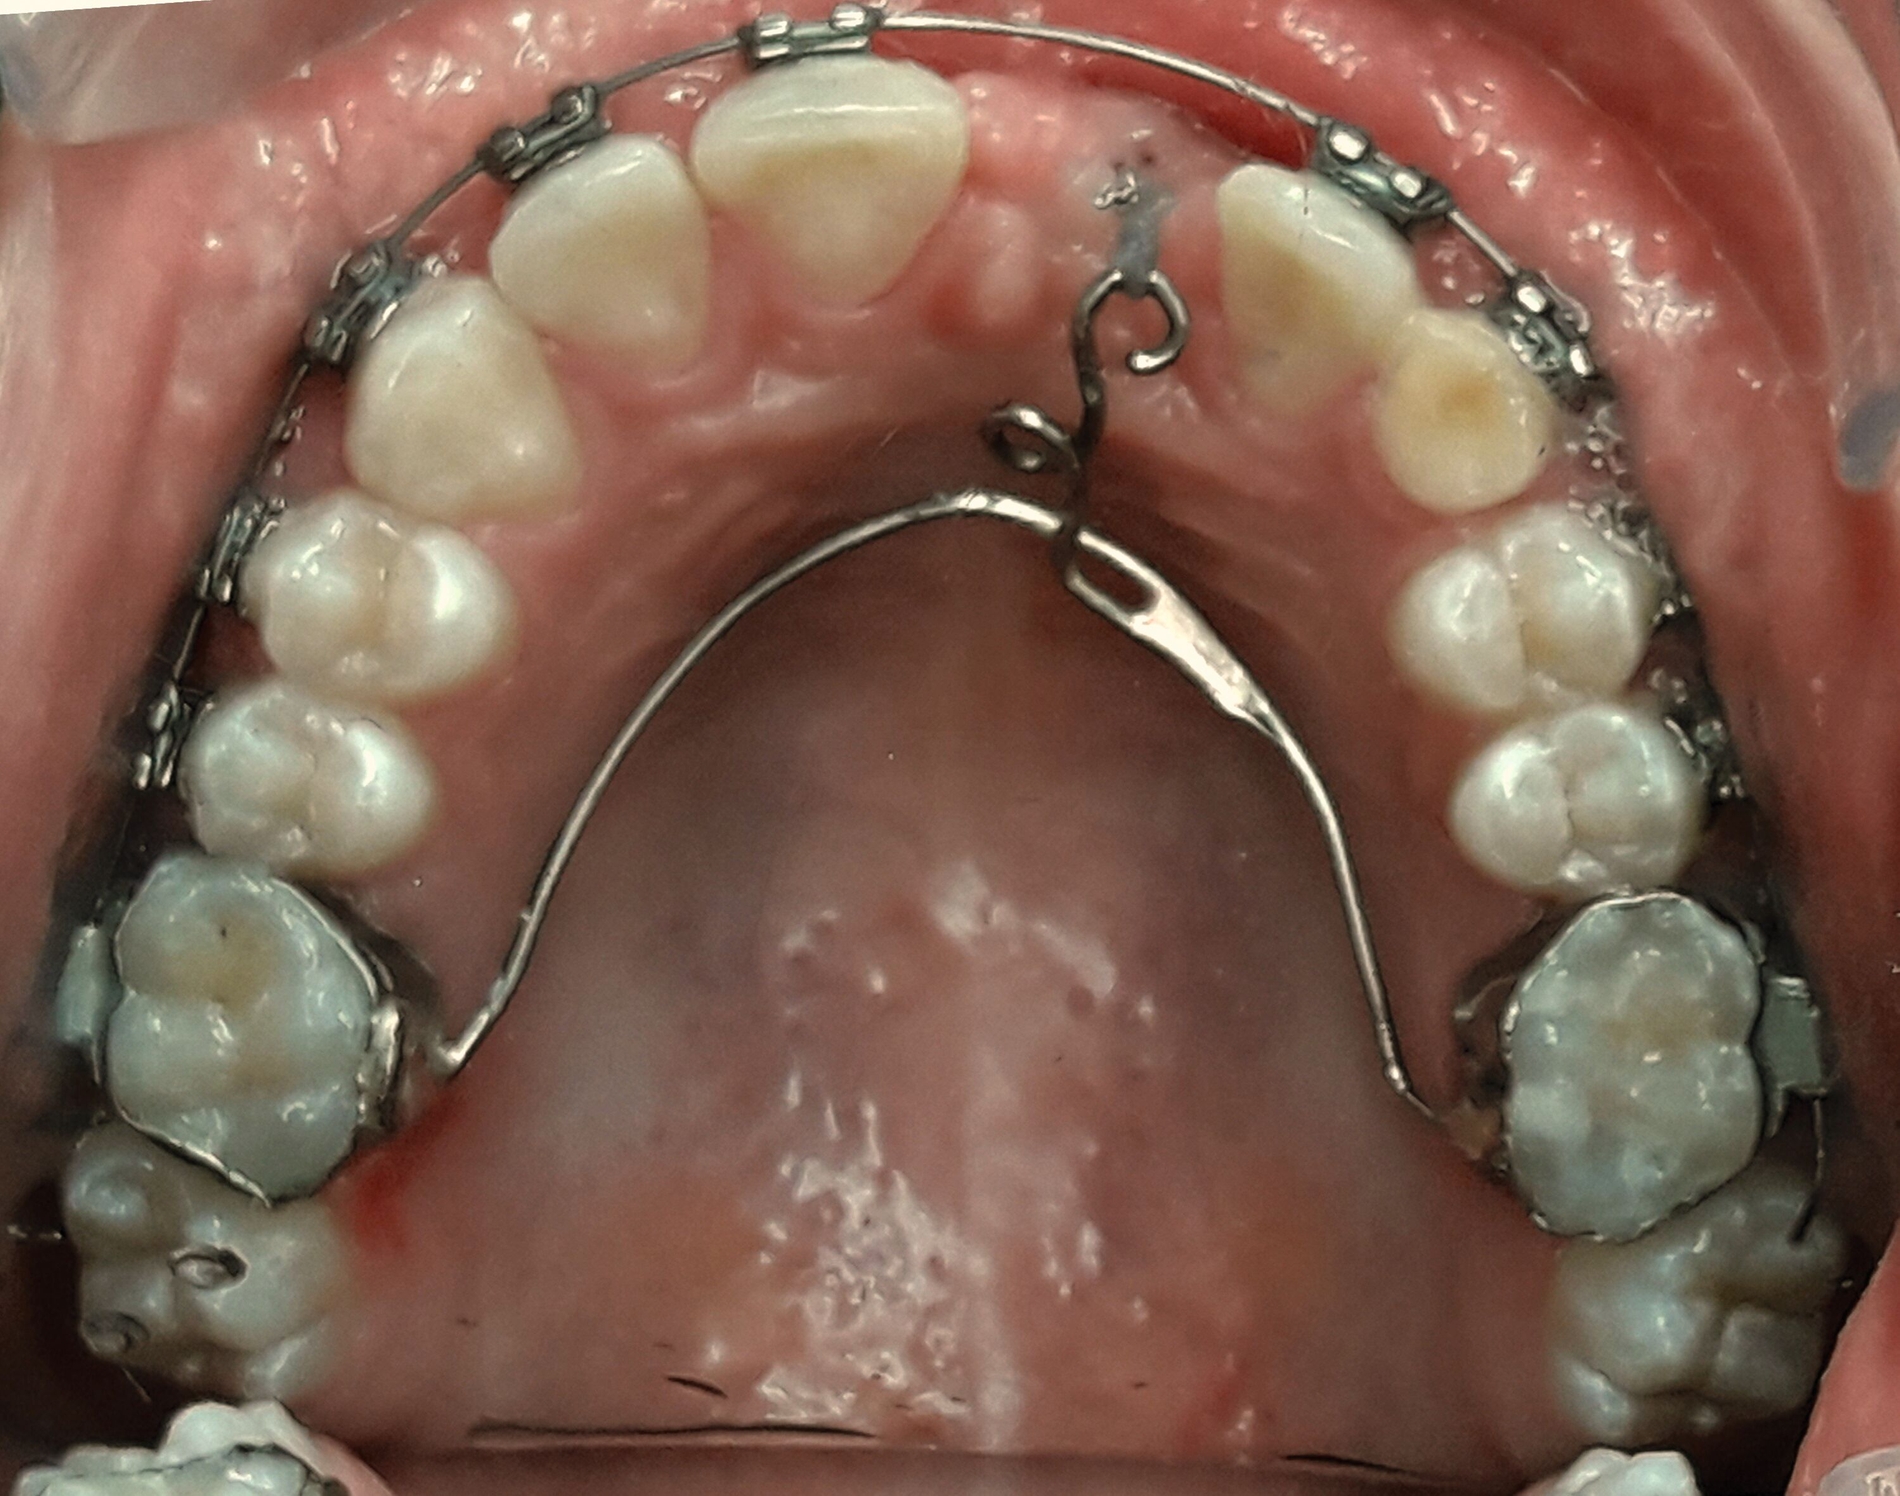

Drei Wochen nach der Operation wurde mithilfe eines modifizierten Palatinalbogens mit einem verlängerten Palatinalarm mit der Traktion des Eckzahns begonnen (Abbildung 4).